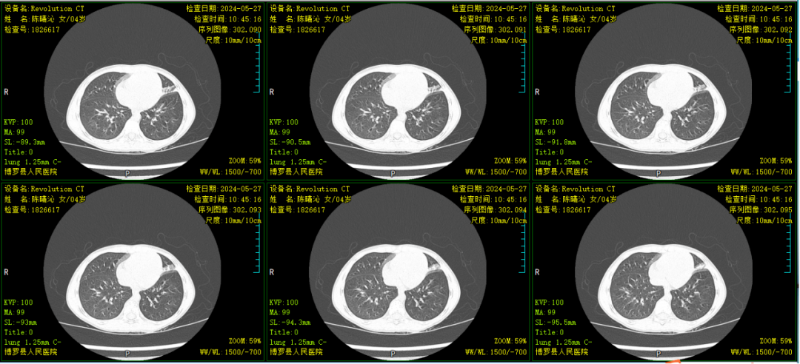

文章配圖

△復查胸部CT示:對比原片,原雙肺病灶基本吸收。

患兒肺部局部實變明顯,予行支氣管肺泡灌洗治療。肺泡灌洗液送檢提示肺炎支原體感染及鼻病毒感染,予加用阿奇霉素抗感染治療。行電子支氣管鏡肺泡灌洗治療9天后,患兒無咳嗽,肺部聽診無啰音,復查胸部CT示:對比原片,原雙肺病灶基本吸收。病情痊愈出院。